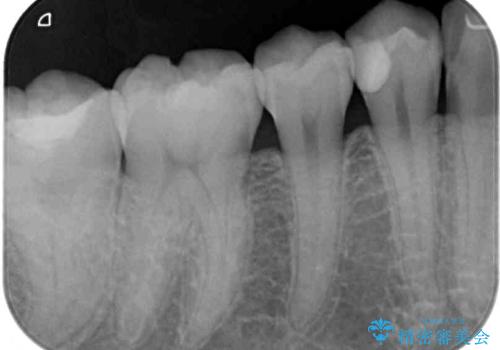

- 奥歯に頻繁に物が挟まるとのことで来院された患者様です。

最近ものが挟まりやすくなったり、冷たいものがしみるようになったりといった症状があり、診査したところ、むし歯や歯質の欠損、不適修復物などが認められました。

精度の高いセラミックインレーによる修復治療を行うこととしました。

処置を行った歯以外にもむし歯と思われる歯が多数ありますが、費用のかかる治療であれば、優先順位をつけて、処置を急ぐ歯から処置を進めて行きました。